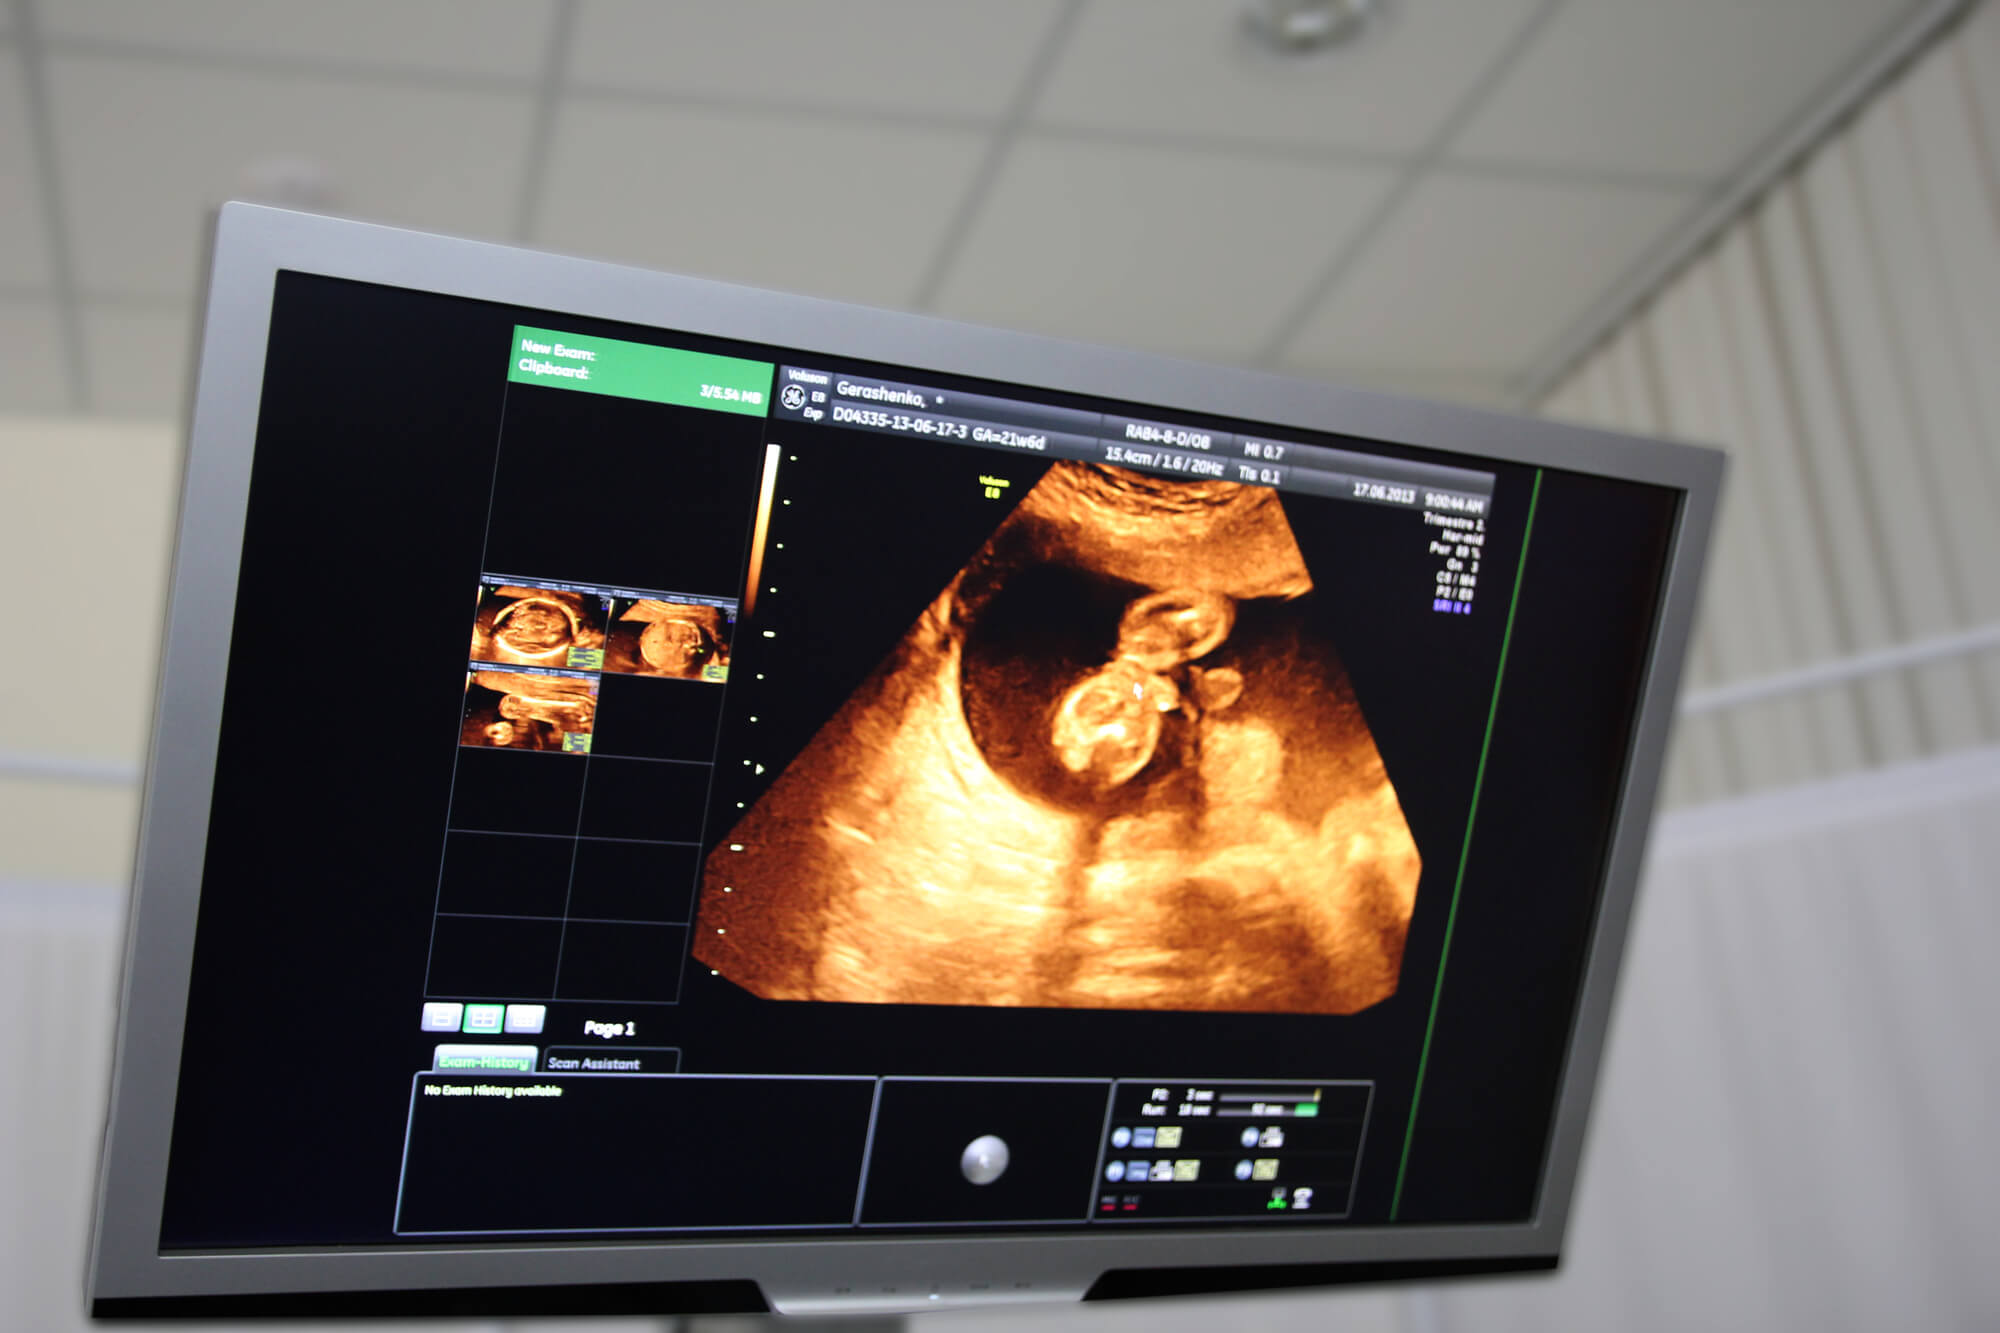

“产检瞬间”+孕中期保胎吃孕酮片管用吗

都说一孕傻三年,我确实是有孕傻的症状怀我家小宝的时候,每次检查结果都很好,可是在五个多月的时间我突然见红了,没有任何症状,只是有血而且还有点多,当时看到有血都吓傻了,一直抹着肚子问老公宝宝会不会有事, -